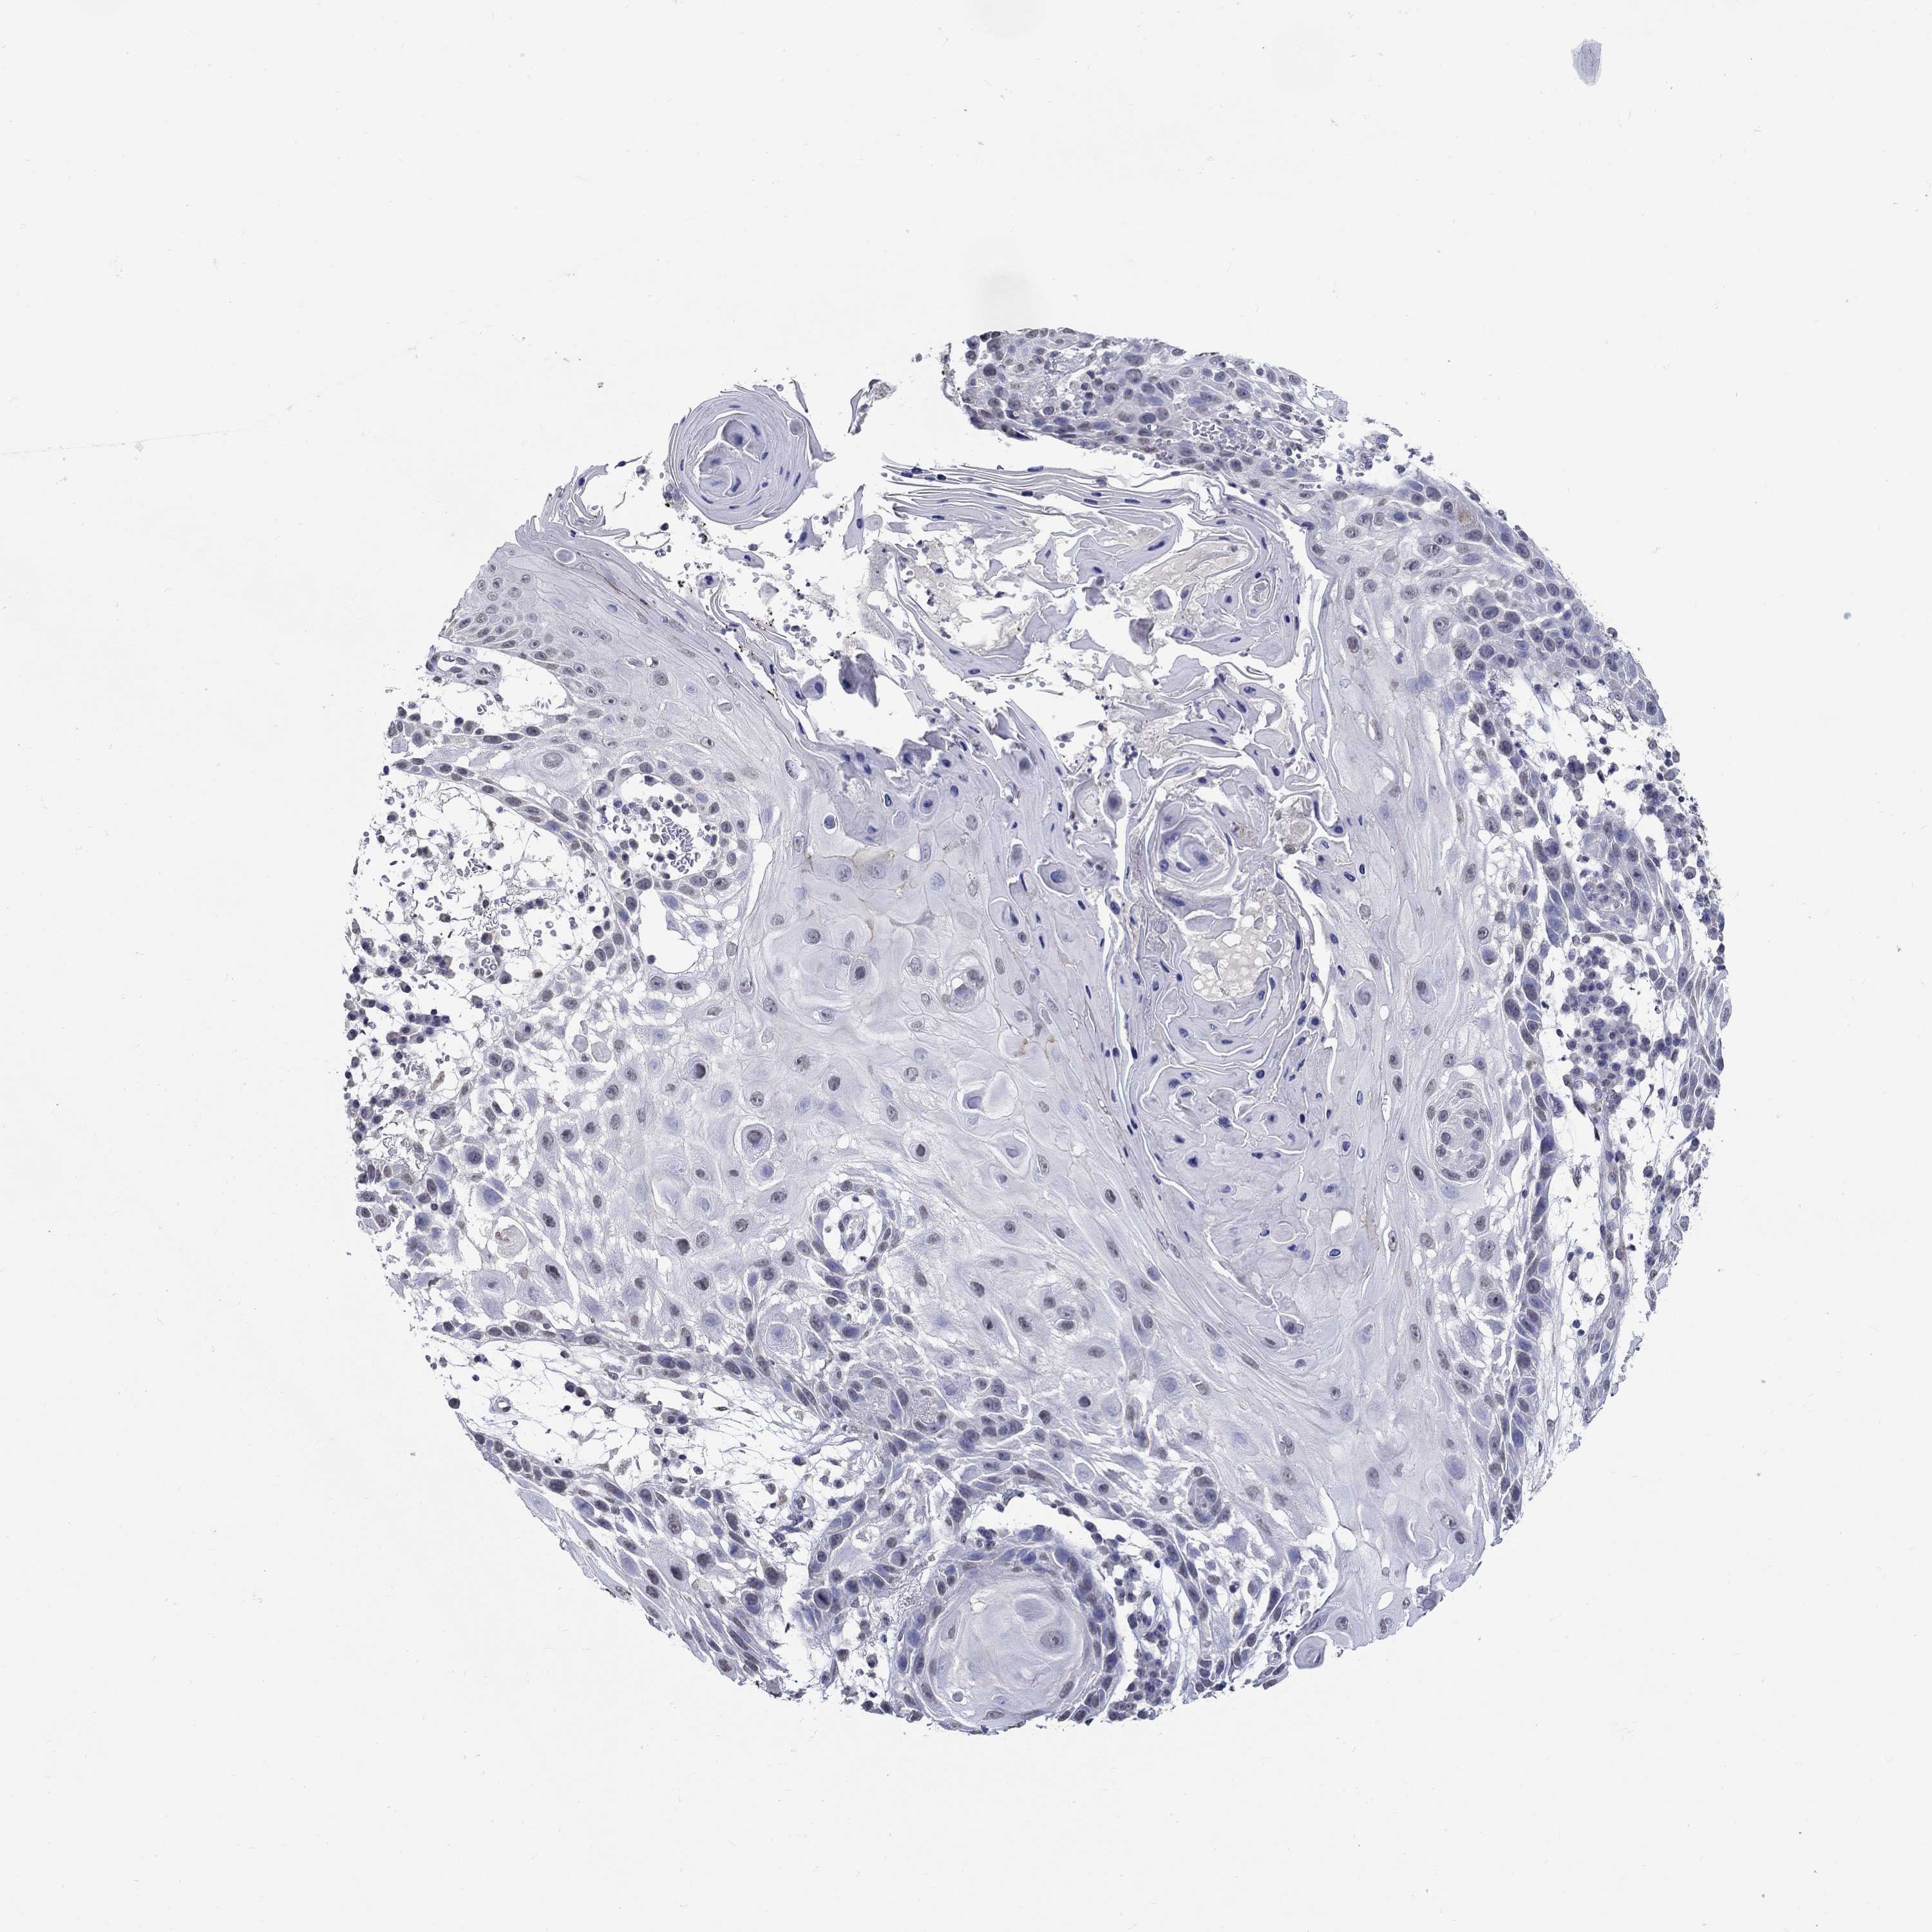

CANCER SKIN CANCER Show tissue menu

Basal cell and squamous cell cancer

SKIN CANCER - Protein expressioni

A mouse-over function shows sample information and annotation data. Click on an image to view it in a full screen mode. Samples can be filtered based on level of antibody staining by selecting one or several of the following categories: high, medium, low and not detected. The assay and annotation is described here.

Each image is clickable and will lead to virtual microscopy that enables deeper exploration of all samples and also displays staining intensity scores, fraction scores and subcellular localization as well as patient and tissue information for each sample.

Antibody HPA018492

Staining

High

Medium

Low

Not detected

Intensity

Strong

Moderate

Weak

Negative

Quantity

>75%

75%-25%

<25%

None

Location

Nuclear

Cytoplasmic/membranous

Cytoplasmic/membranous,nuclear

Basal cell carcinoma

Squamous cell carcinoma, NOS